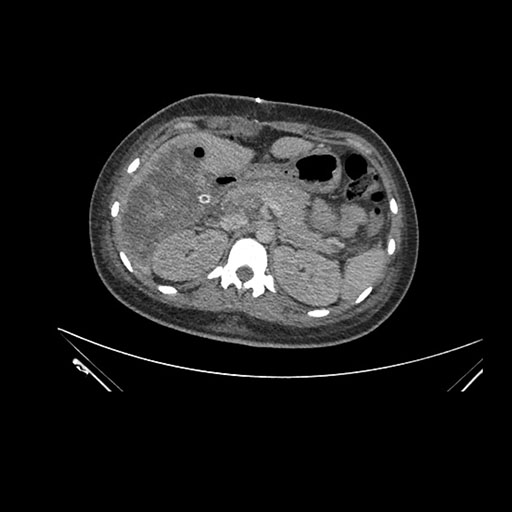

Axial Venous

Imaging analysis

Based on initial findings, which issue(s) would you be most concerned about?